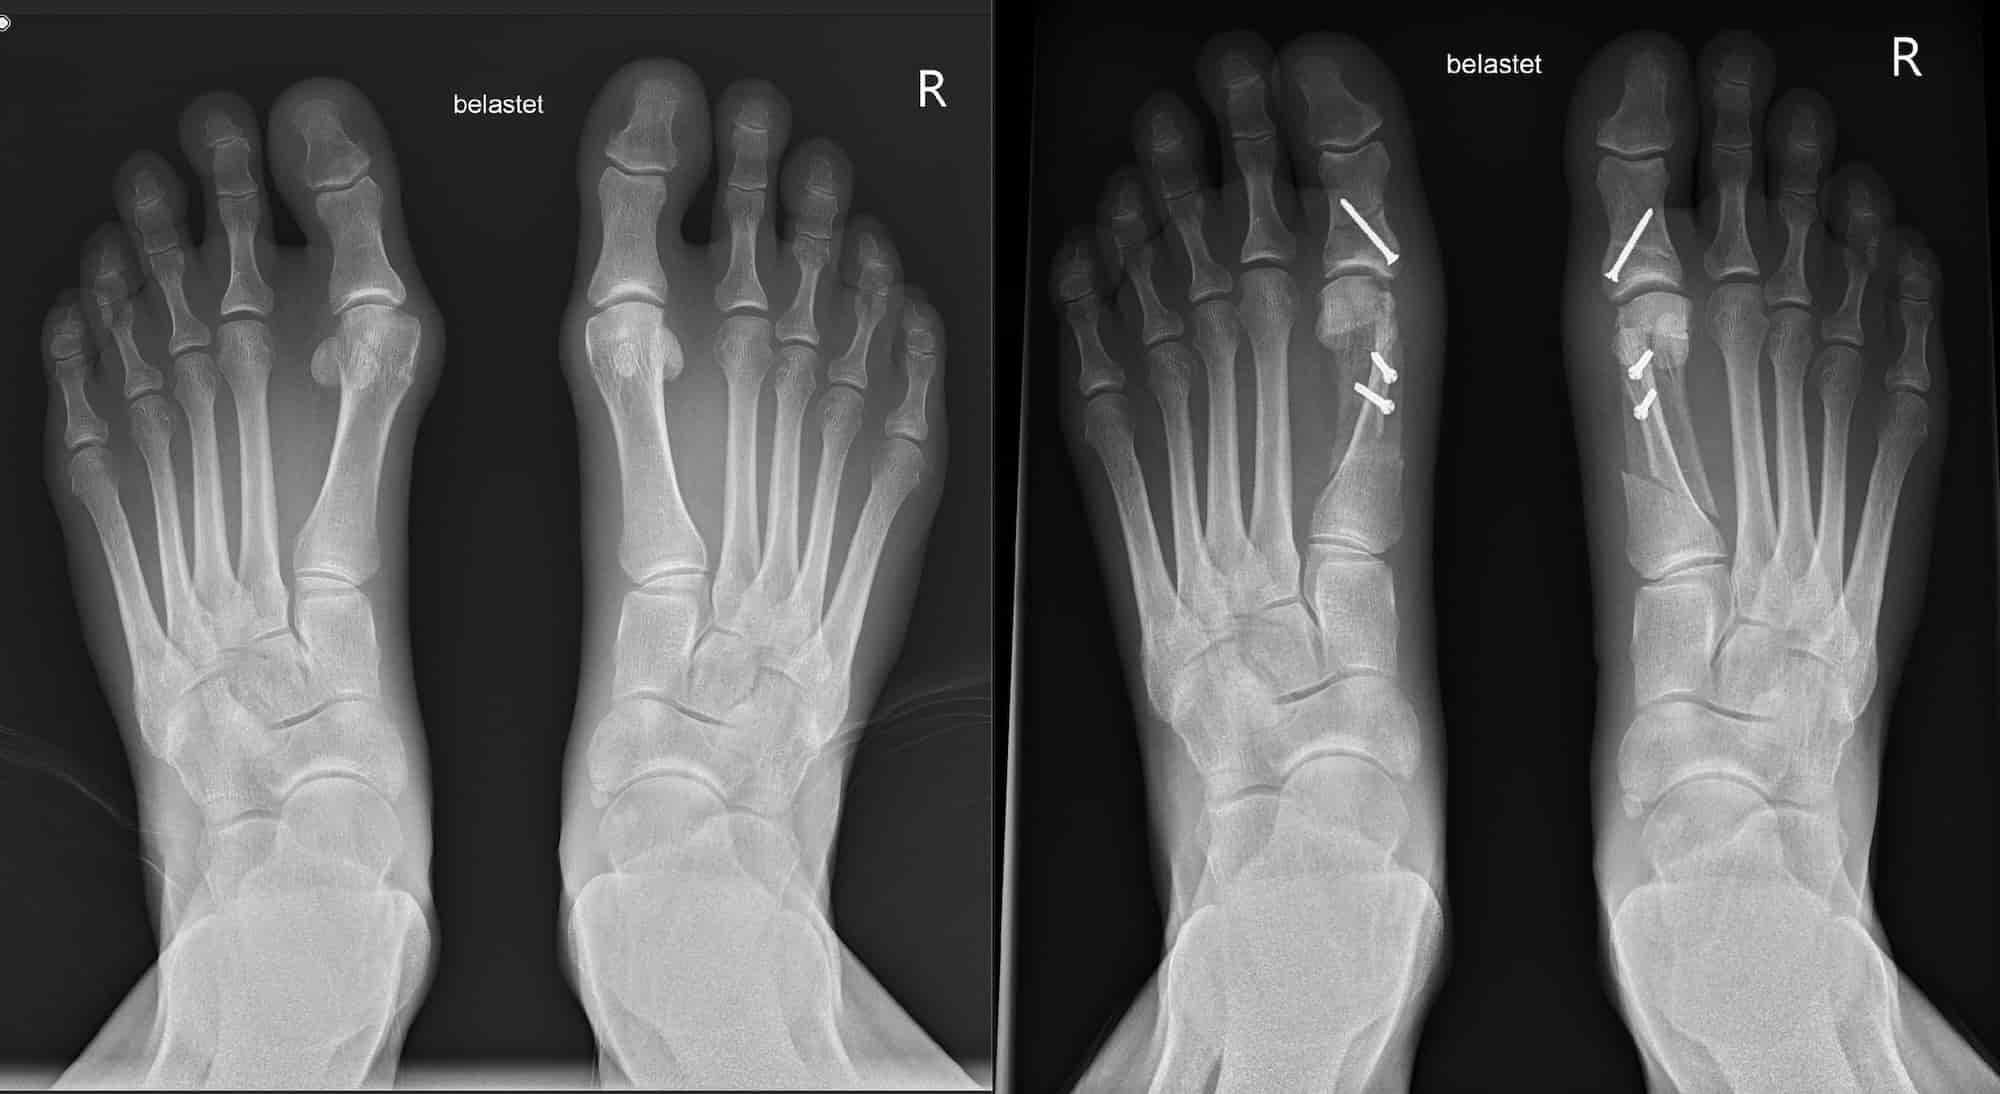

On the second day, the anesthesia wears off and the first pain slowly sets in. Thanks to the painkillers, however, everything is bearable and less bad than I had imagined. I'm amazed that a bone in each foot has been sawn through, moved and fixed with screws and yet I'm not in any worse pain.

The first trail runs in spring are still a bit bumpy, but by early summer I've all but forgotten about the operation and in May I finish physiotherapy after seven months. My feet are coping with everything, no longer hurt and the swelling is barely noticeable. I no longer have any problems even after longer tours. Then a minor setback at the end of July: now that the swelling has finally subsided, two screw heads become noticeable under the skin on my left foot and I notice pressure points. Over a few weeks, the pain at these points increased because the tissue became more and more irritated.

The screws could simply be removed immediately and the small stitch would then take about two weeks to heal. However, our trail running vacation is just around the corner and I don't want to spend two weeks at a campsite in the Engadin while Falko explores the trails on his own. So we come up with an alternative. With approx. 5 mm thick padding around the pressure points, I can run without pain and together we hit the trails in the Engadin! My personal highlight is our trail run through Val Roseg. We combine our return journey with an appointment at the clinic and after just half an hour I have both screws off. A week later, I'm already hiking through the mountains again, while Falko is out trail running around Saas-Fee.